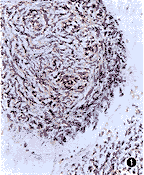

各种脱钙液在微波/室温脱钙时间分别为A液:1分钟×20次/24小时×7次,B液:1分钟×6次/24小时×2次,C液:1分钟×6次/24小时×1次,D液:1分钟×4次/24小时×1次。脱钙后的骨组织对保持组织完整结构以A液、D液较好,其中A液最好,对骨组织几乎无损害。B液和C液对骨组织破坏严重,使结构看不清。在进行免疫组化染色后发现,以A液对保存组织中抗原物质最好(图1~3),最差的为C液。

图1 骨肉瘤组织经免疫组织化学反应,骨形成蛋白定位比较准确,阳性强度高,背景干净 SP法 ×200